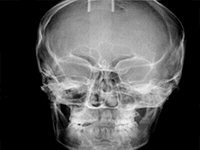

Pro Patient: Our state-of-the-art cone-beam computed tomography (CBCT) technology could selectively image the sinus, oral maxillofacial, para-nasal sinuses, ear & throat regions.